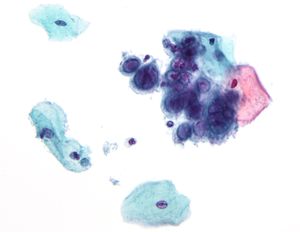

- HPV (Human Papilloma Virus)— skin and mucosal contact. 'High risk' types of HPV are known to cause most types of cervical cancer, as well as anal, penile, and vulvar cancer, and genital warts.

- Molluscum contagiosum (molluscum contagiosum virus MCV)—close contact